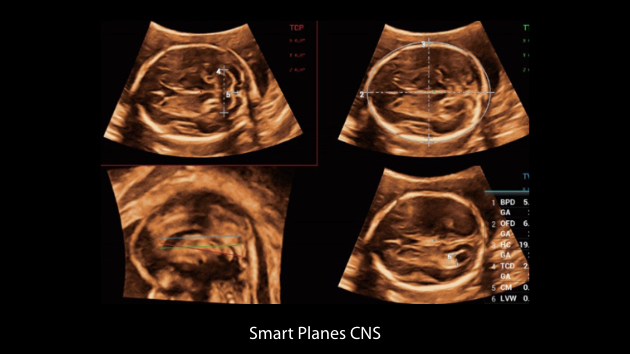

De Nuewa I9, speciaal ontworpen voor vrouwen en neonatale gezondheidszorg, biedt een innovatieve ervaring van binnenuit. Deze innovaties zijn ontwikkeld op basis van diepgaande inzichten in complexe klinische scenario's en bieden nauwkeurige en tijdige antwoorden, evenals een uitstekende effici?ntie en opmerkelijke gebruikerservaring.